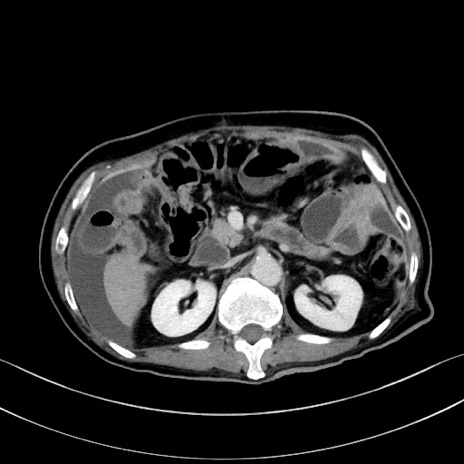

症例28(横断像)

【症例】60歳代男性

【主訴】嘔吐

【現病歴】胃癌にて胃全摘後。食思不振が悪化し、夜中に嘔吐することがある。

【既往歴】胃癌、胃全摘、脾摘、胆摘後

【データ】WBC 5900、CRP 10.56